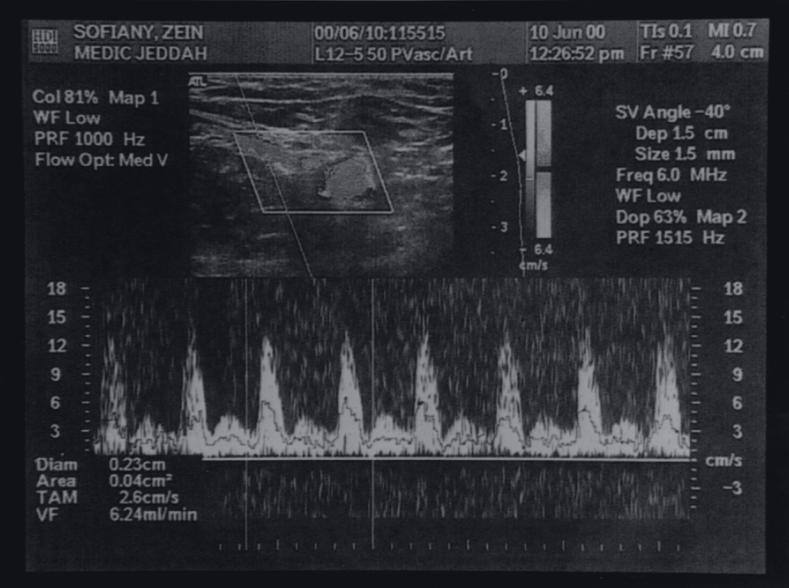

术后,受者子宫动脉多普勒超声图像

图源:参考文献 4

然而,术后医生们发现供者的左侧输尿管却出现损伤,医生判断是因为输尿管离子宫动脉很近,因此子宫切除术中的操作不当,造成了输尿管的损伤。

祸不单行,在移植后 99 天,受者也出现了问题。受者新子宫体部的血管出现一个急性的血栓形成,并导致了栓塞,整个子宫坏死,医生不得不为她行子宫切除术。 [4]